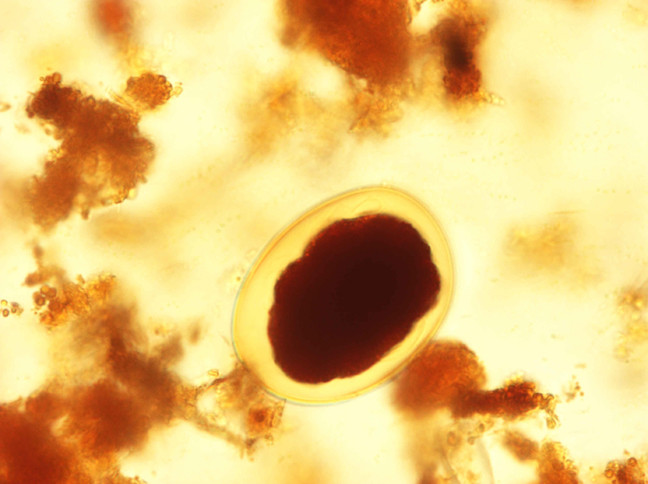

- 40x

Enterobius

Notice the ova is flattened on one side